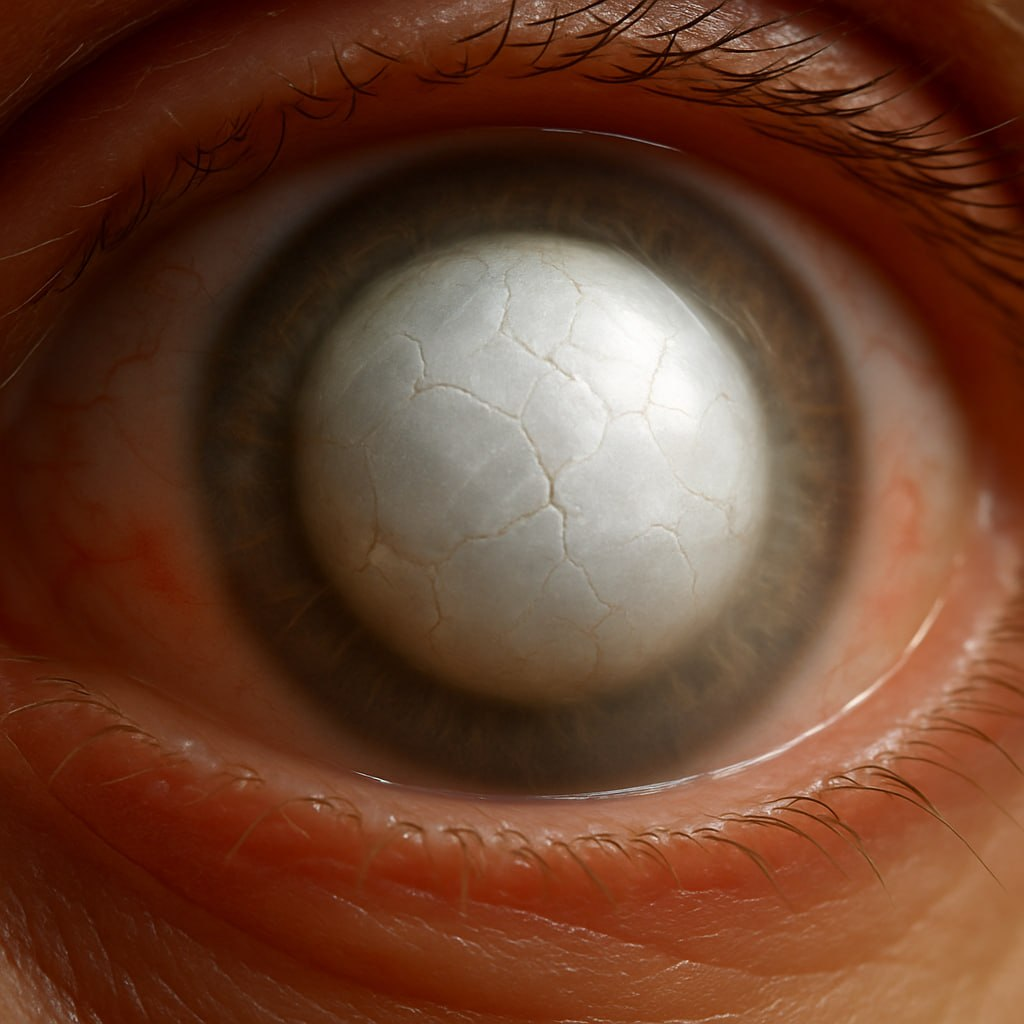

Это крайняя стадия болезни. Хрусталик полностью мутнеет, его белковые массы начинают распадаться, капсула становится рыхлой. Иногда жидкость внутри «растекается», и глаз выглядит молочно-белым. На этом этапе восстановить зрение уже невозможно — зрительный нерв и сетчатка, как правило, давно атрофированы. Но сам хрусталик превращается в источник проблем.

· Косметическая проблема. Молочно-белая катаракта заметна окружающим, и для некоторых пациентов это тоже важный фактор.